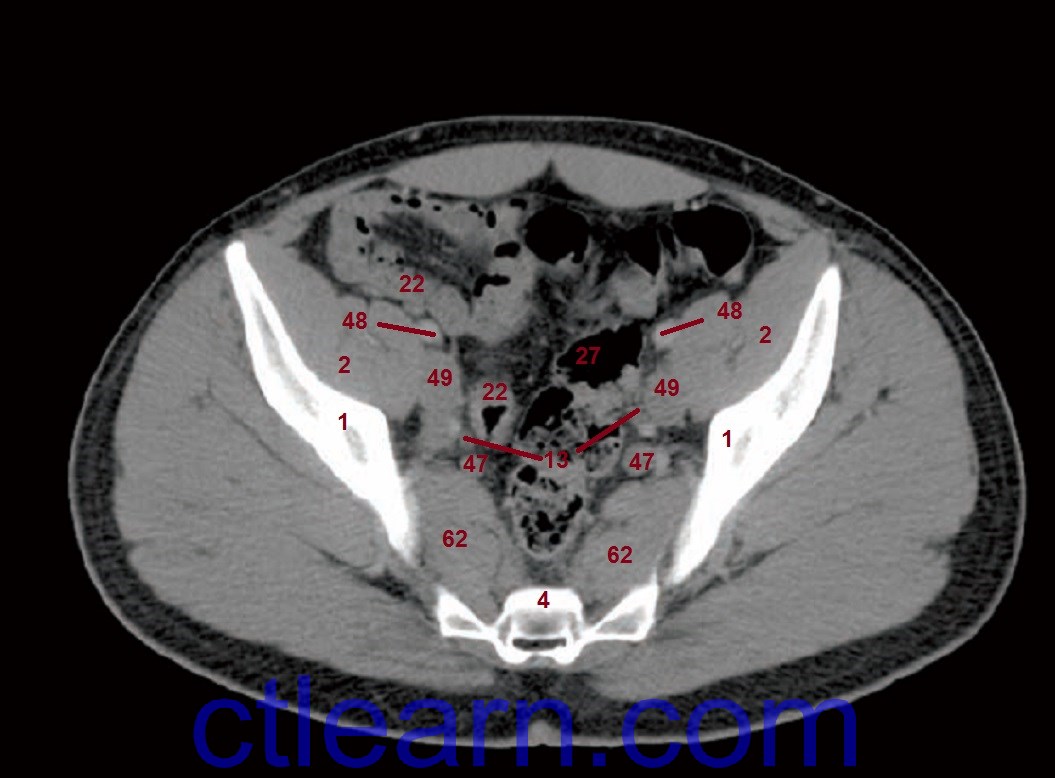

Position n 2 110 фото